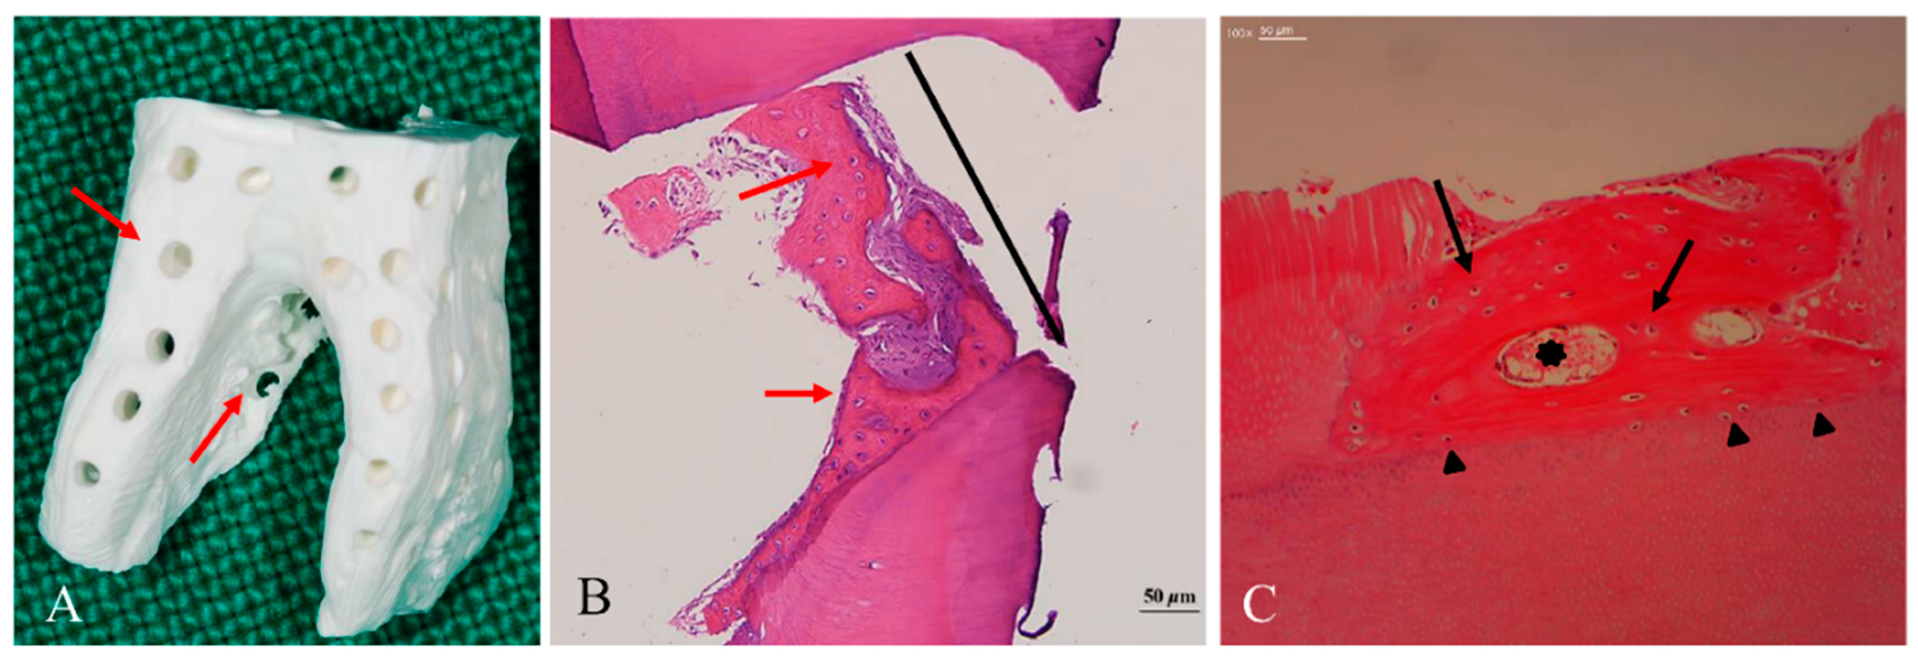

Figure 5.

Histological findings of dentin block grafts into the skeletal sites [63]. (A) Macropores (300 µm, red arrow) on the dentin block that penetrated from the surface to the pulp space provided the space for vascular invasion. (B) At 8 months after the graft, the macropores (300 µm, black line) were filled with newly formed osteoids with embedded active chondrocyte-like cells (red arrow) that closely contacted the inner wall of the macropore. (C) At 3 months after the graft, a newly formed osteoid, which had osteocytes (black arrow) and vessels (black asterisk), had been deposited on the dentin block surface. Cellular fusion without fibrous tissue invasion was observed on the border between the osteoid and the dentin matrix (black arrowhead).